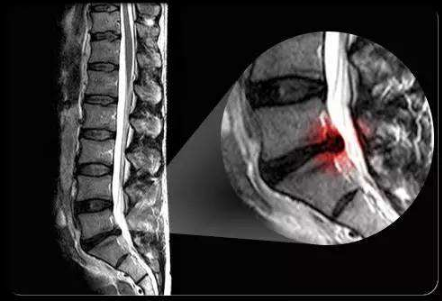

X線、CT、MRI檢查

坐骨神經痛圖片